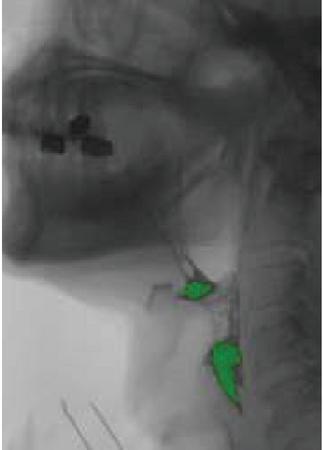

images

Figure 4 Based on improved three-frame difference experiment results.

Figure 5 Enlarged display of experimental results.